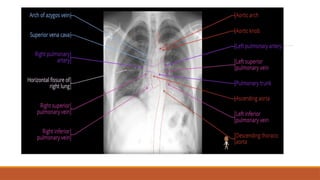

H-HILUM AND MEDIASTINUM

H-HILUM

MEDIASTINUM

MEDIASTINAL CONTENTS